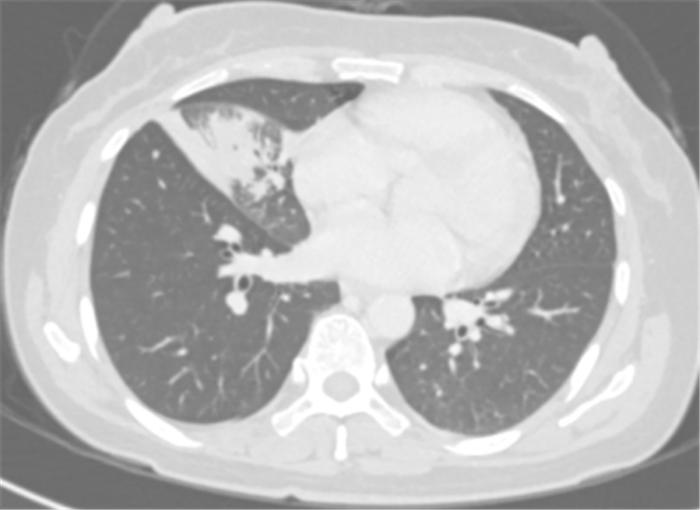

覃寿明教授团队为李女士进行了4个周期的化疗联合免疫新辅助治疗。覃寿明介绍,肿瘤的免疫治疗是通过激活人体免疫系统,依靠自身免疫机能实现杀灭肿瘤细胞和肿瘤组织。免疫治疗的作用更持久,副作用也相对更低。

经过4个周期的治疗后复查发现:李女士的病灶明显缩小,实现了降低肺癌分期。

免疫联合化疗新辅助治疗4周期后胸部CT